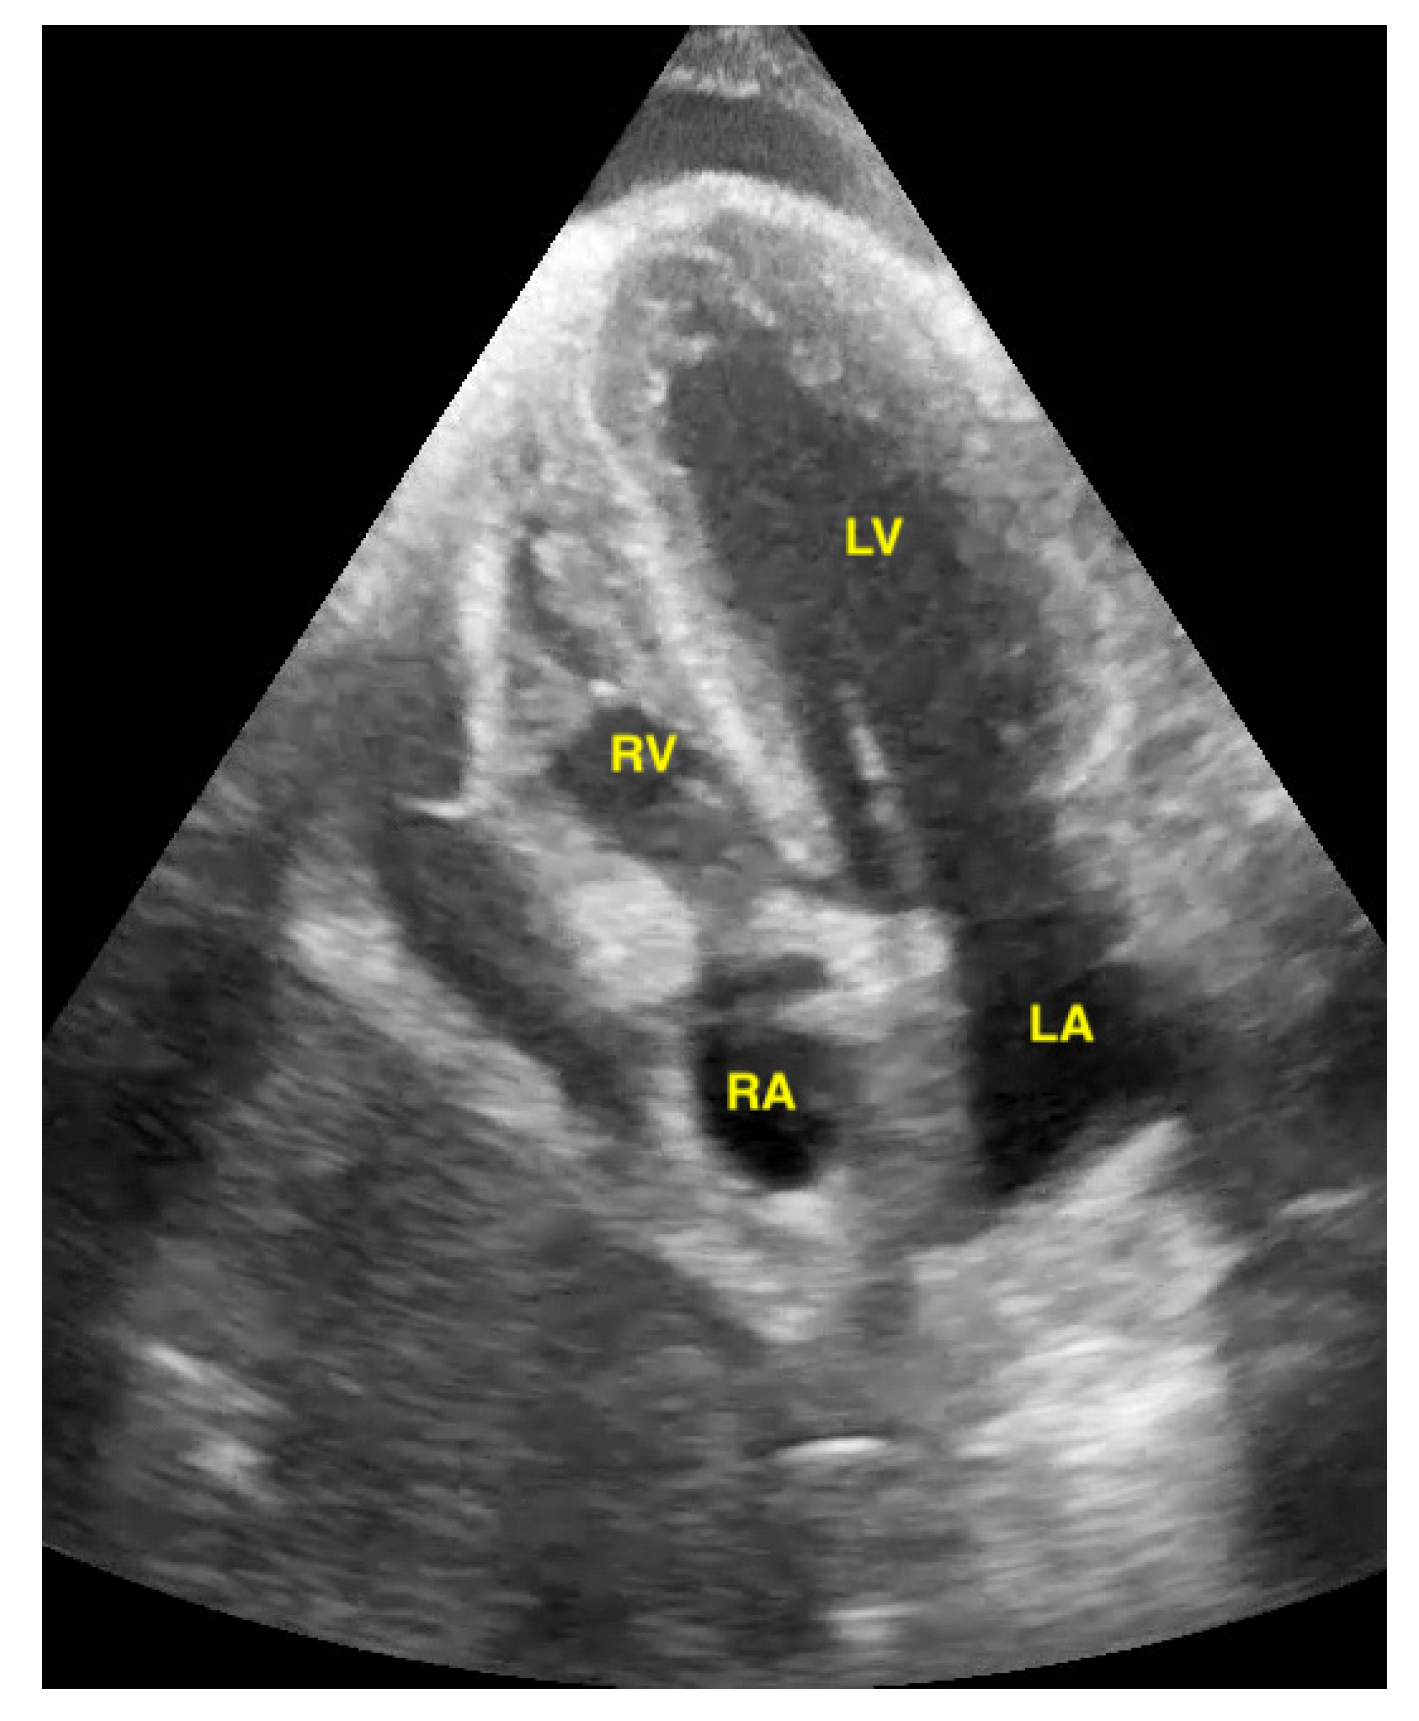

Figure 9.

Pericardial effusion in apical four chamber view compresses the right atrium slightly (RA = right atrium, LA = left atrium, RV = right ventricle, LV = left ventricle).